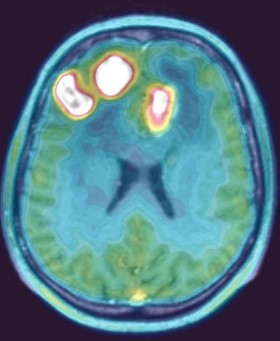

ПЭТ КТ головного мозга с метионином: подготовка и диагностика Позитронная эмиссионная томография - это метод, основывающийся на исследовании функциональной и метаболической активности головного мозга .

Высокоточным методом диагностирования новообразований в головном мозге на сегодняшний день считается ПЭТ/КТ с метионином . Обследование дает возможность выявлять рак на ранних стадиях, что значительно улучшает показатели результативности лечения . Успешно применяется ПЭТ и для исследования сердечно-сосудистой системы и неврологических заболеваний .

Цель исследования — определение информативности ПЭТ/КТ (ПЭТ) с 11 С-метионином в диагностике продолженного роста церебральной глиомы при помощи roc-анализа, а также сравнение относительных частот трех видов поражений . . .